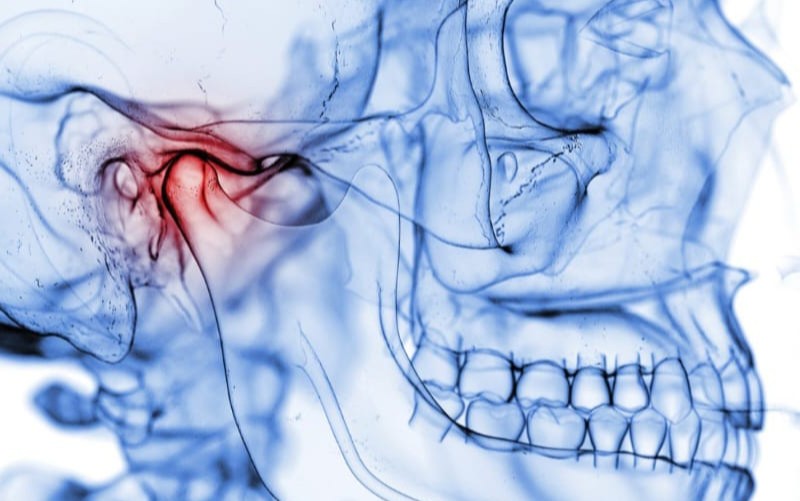

Facial Trauma Treatment

Expert management of facial injuries including fractures and soft tissue repair, ensuring functional restoration and optimal cosmetic outcomes.

TMJ Disorder (Jaw Joint Disorders) Treatment in Thane